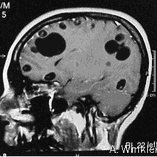

The normal life cycle entails a human final host with the adult tapeworm (taeniasis) and a pig intermediate host with the metacestode larval stage (cysticercosis). People get infected by the consumption of undercooked infected pork. Pigs get infected by the consumption of infected human stool with tapeworm eggs/proglottids. Unfortunately, people can also act as dead end intermediate host, after ingestion of tapeworm eggs via fecal-oral contamination, whereby the larval stages have a tendency to settle in the human central nervous system (Murrell, 2005). The latter condition, neurocysticercosis (NCC) is responsible of about 30% of acquired epilepsy cases in endemic areas (Ndimubanzi et al., 2010).